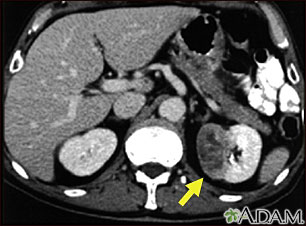

This CT scan of the abdomen shows a tumor in the left kidney (called hypernephroma, or renal cell carcinoma). It is located on the lower right side of the picture.